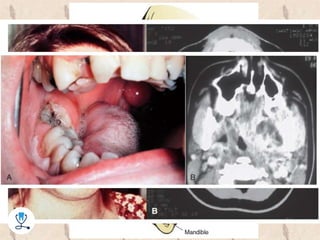

•‫لودویگ‬ ‫آنژین‬

–‫صورت‬ ‫به‬ ‫عفونت‬ ‫با‬ ‫مندیبوالر‬ ‫پری‬ ‫فضاهای‬ ‫درگیری‬2‫طرفه‬

–‫هوایی‬ ‫راه‬ ‫انسداد‬ ‫امکان‬

–‫بزرگ‬ ‫خیلی‬ ‫تورم‬

–‫تنفس‬ ‫و‬ ‫بلع‬ ، ‫بزاق‬ ‫ریزش‬ ، ‫تریسموس‬ ‫مشکالت‬

–‫درمان‬:‫هوایی‬ ‫راه‬ ‫نمودن‬ ‫باز‬‫و‬I&D(Ab‫حمایتی‬ ‫نقش‬ ‫تراپی‬)